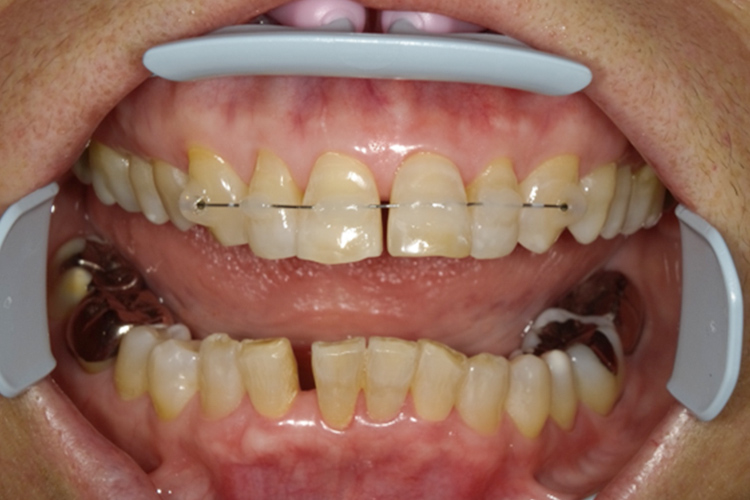

矯正前

矯正後

前歯の傾斜治療

ブラケット装置装着

治療後